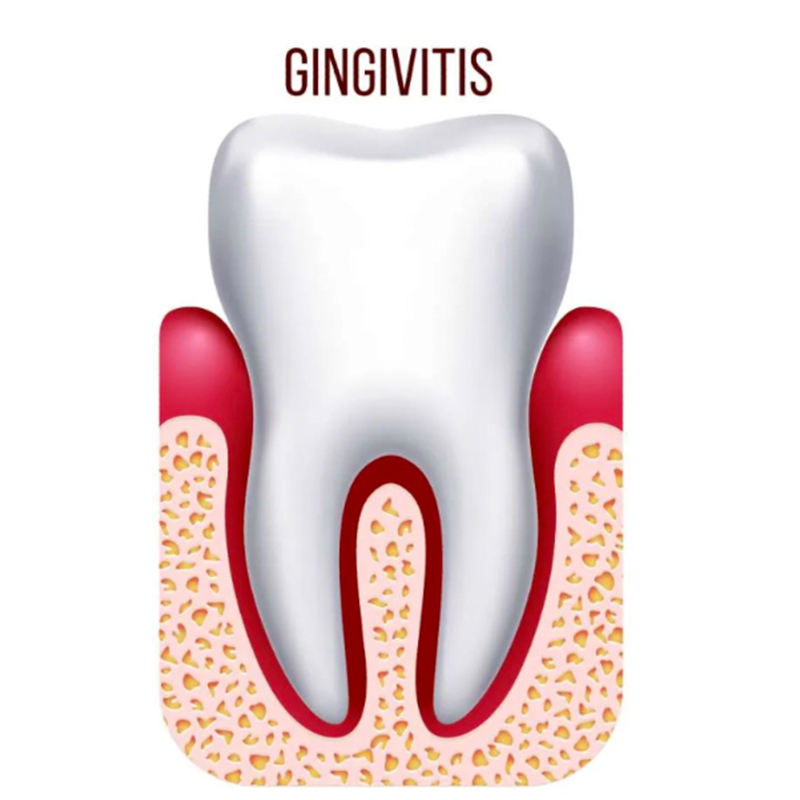

Gingivitis

Es la inflamación superficial de la encía. Su principal señal de alerta es el sangrado y, si no se trata con una limpieza profesional y una adecuada higiene oral, puede progresar hacia la periodontitis.